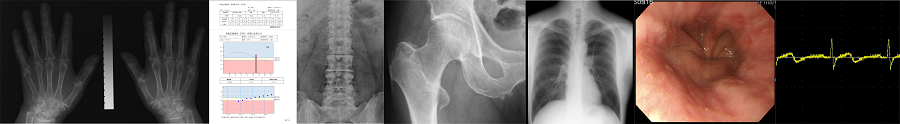

骨密度(DIP法/CXD法)のオンライン解析サービスのご案内

骨密度解析に対するご意見を沢山頂いております。ご要望にお応えする為のに考えたのが、当社のオンライン骨密度解析サービスです。